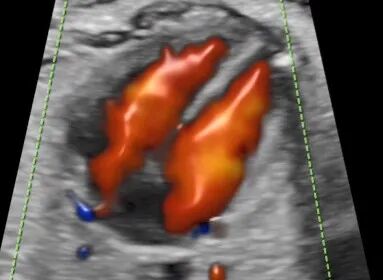

煊流成像技术:SlowflowHD:快速、直观显示微小血管

煊流成像——彩色血流高清立体成像,脏器内的血流以立体形式展现在我们眼前。

脐带内血流立体成像